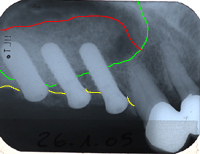

Abb. 1 - ortsständiger Knochen im Oberkiefer rechts vertikal 2 bis 5 mm.

Verlauf des Kieferhöhlenbodens vor

Sinuslift

Verlauf des Kieferkammes

-Gebiet zwischen gelber und grüner

Linie: ortsständige Knochenhöhe.

neuer Verlauf des Kieferhöhlen-

bodens nach Sinuslift.

-Gebiet zwischen roter und grüner

Linie: Knochenaufbau, Sinuslift.